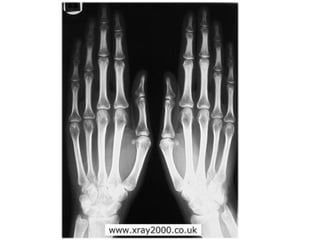

Gout

• Gout is a disease that results from an

overload of uric acid in the body. This

overload of uric acid leads to the

formation of tiny crystals of urate that

deposit in tissues of the body, especially

the joints. When crystals form in the joints

it causes recurring attacks of joint

inflammation (arthritis). Chronic gout can

also lead to deposits of hard lumps of uric

acid in and around the joints and may

cause joint destruction, decreased kidney

function, and kidney stones.